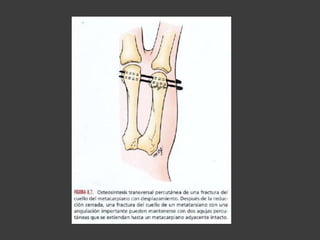

Fx del cuello de los

metacarpianos

 Tto fx inestables

- MCF en 90°

- Compresión axial de 1° F con la cabeza

MC

- Inmoviliza con yeso y/o férula digital con

MCF en 90° e IFP en extensión por 3

semanas

- Rx control al 7° dia

- No se debe inmovilizar con el método

de Jahss (90°-90°)

 OTS indicación

- Angulación severa (> 60°-70°)

- Mal alineamiento rotacional a lateral

- Evaluación tardía (+ de 5-7 días)